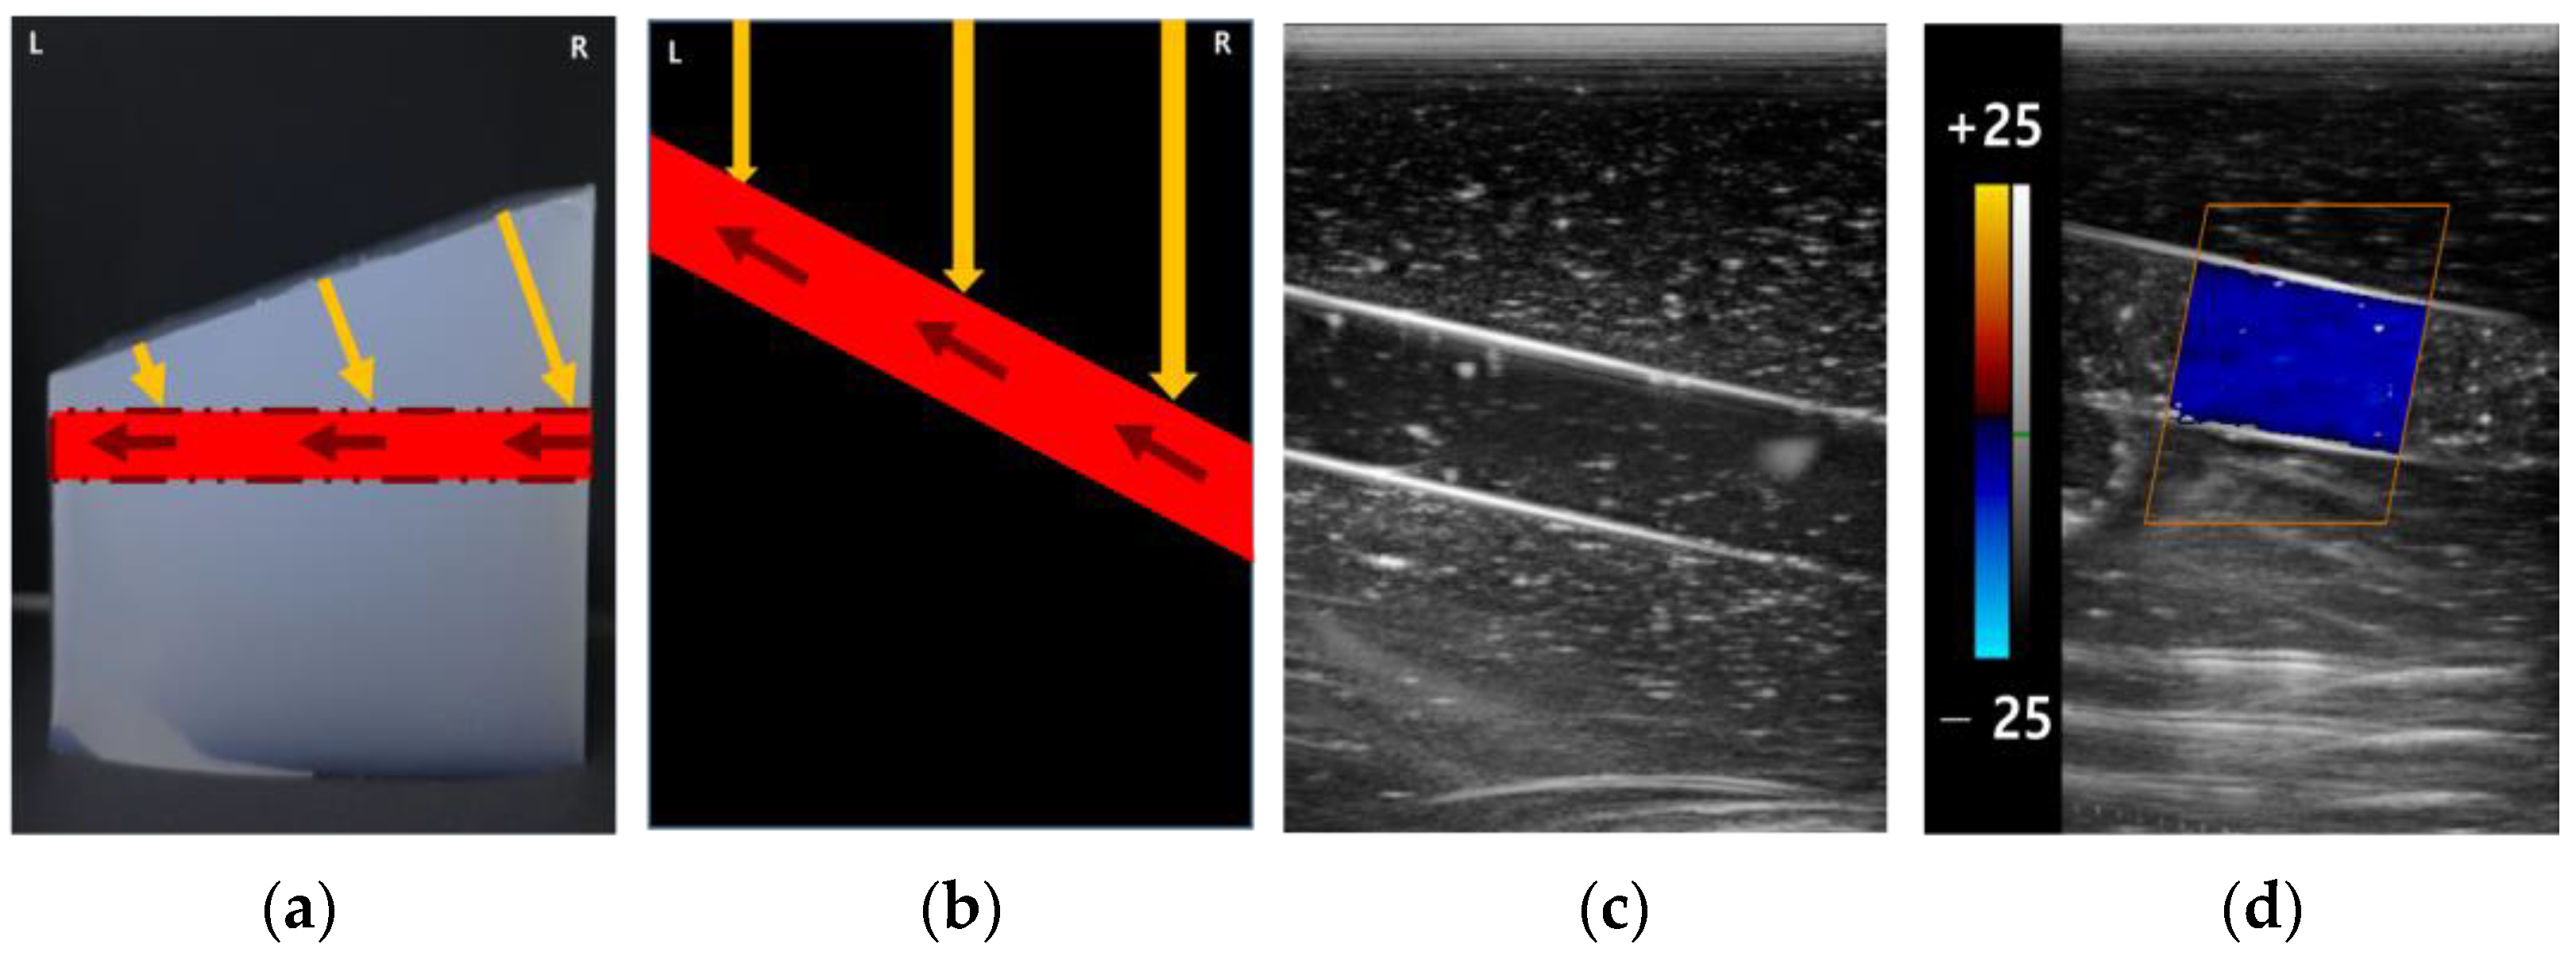

2.4. Acquisition of Ultrasound Image and Analysis

3.2. The Color Doppler Results

3.2.1. Color Box